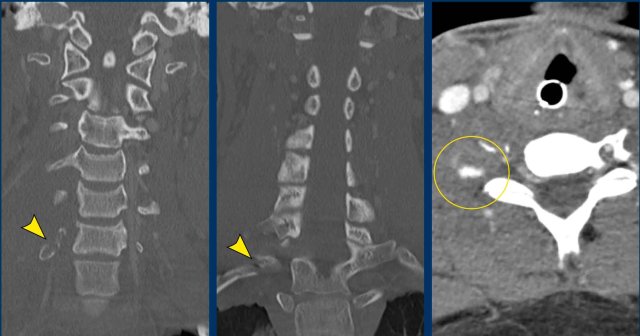

Case

This young man was involved in a motocross accident.

He was admitted to the ICU with multiple injuries.

After three days he regained consciousness and a paresis of his right side was noted, which could not be explained by any cerebral injury.

He also had a Horner on the right side.

Images

The CT at admission showed fractures of the transverse process of C7 and of the first rib (arrowheads).

On the CECT there was contrast extravasation indicating active bleeding (circle).

Continue with the MRI...

First an ultrasound of the neck was performed to look for nerve avulsion, but this examination was limited by traumatic changes in this area.

Subsequently an MRI was performed.

The axial image shows enhancement of nerve roots indicative of a brachial plexus injury.

Also note the injury to the right paravertebral soft tissues.

Continue....

Image

In addition the T2W-image shows some subtle high signal in the myelum on the right (arrow).

This was regarded as post traumatic myelopathy and could also be an explanation for the right-sided Horner.